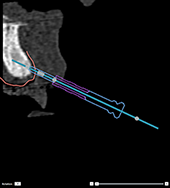

Incorrect: the sleeve of the anchor

pin is not attached to the radiographic guide and will not be

attached to the template. |